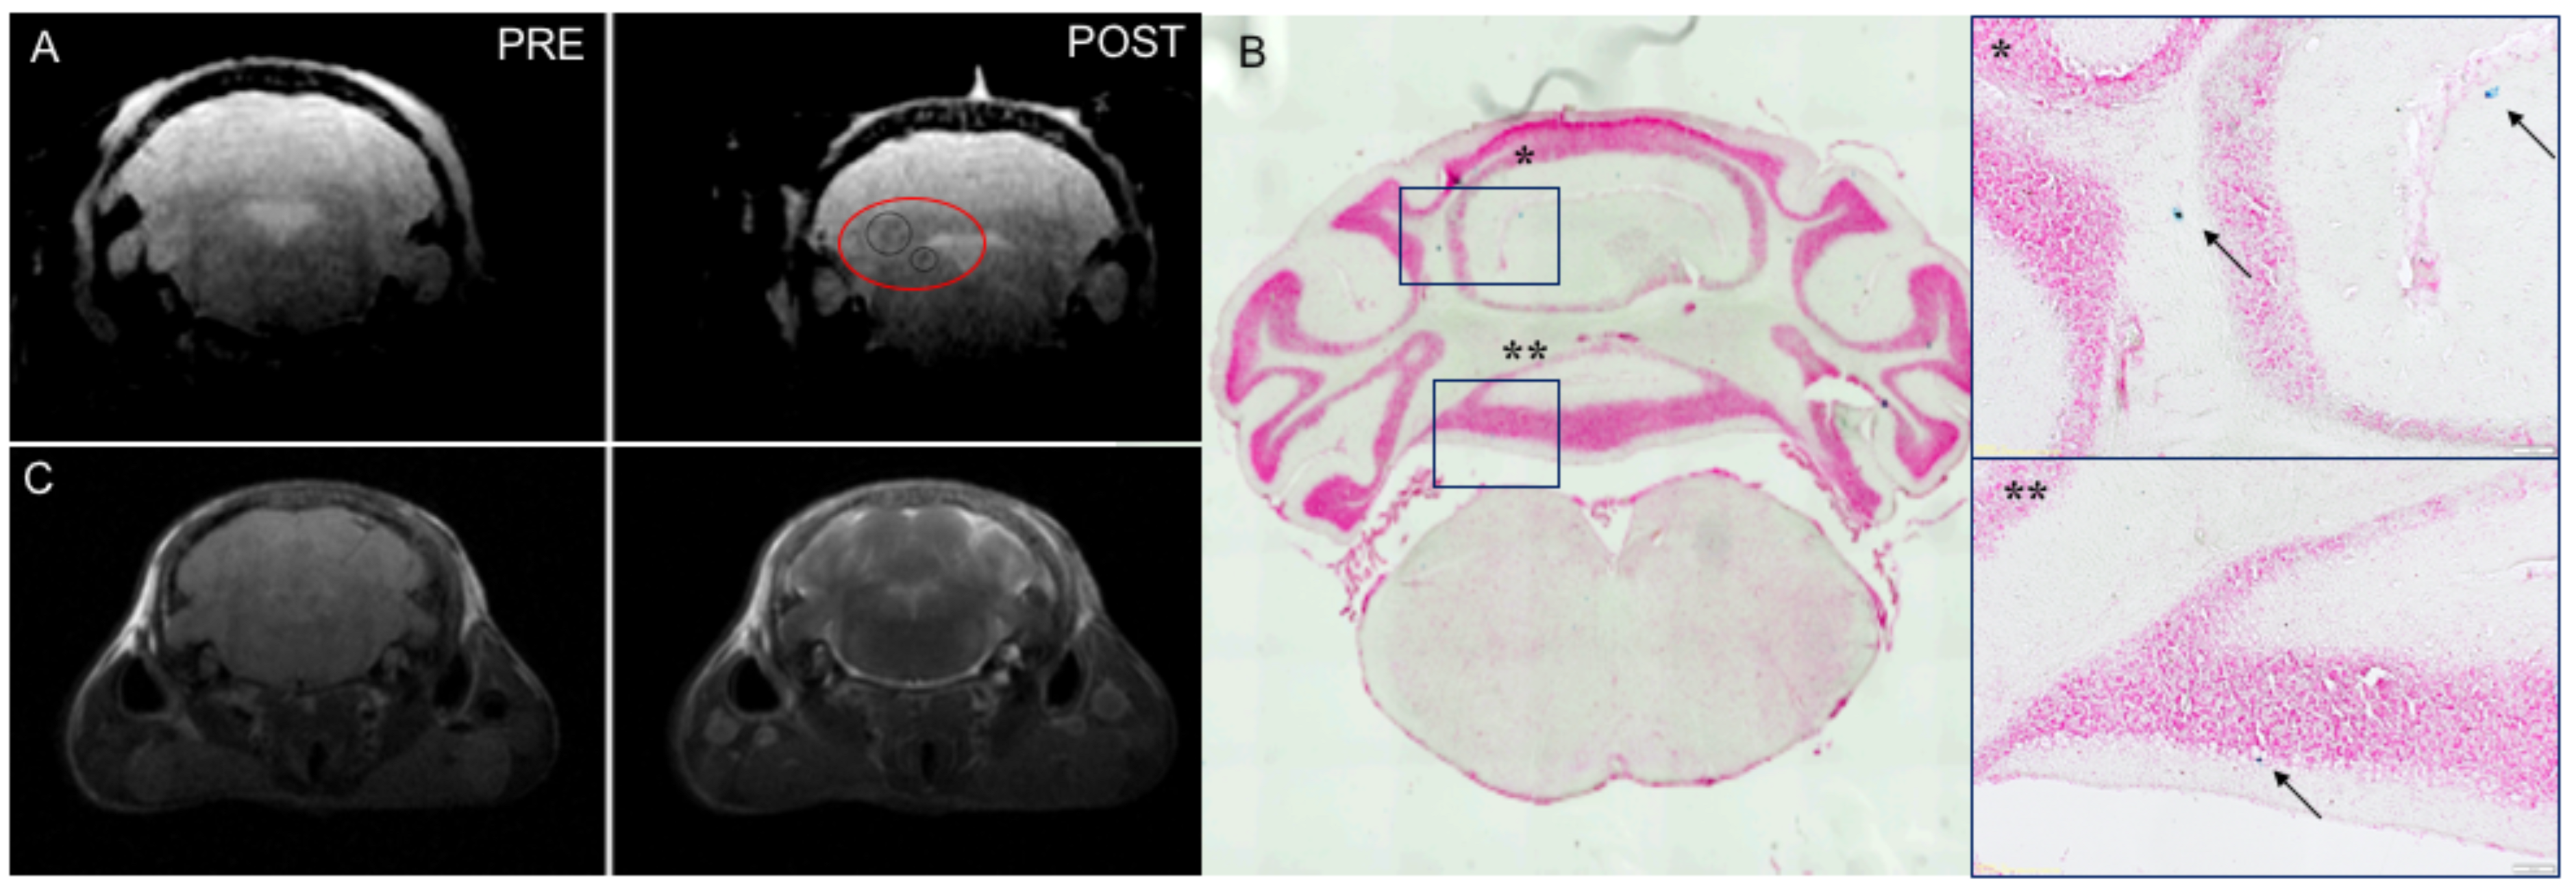

2.7. Magnetic Resonance Imaging (MRI)

2.8. Neuropathology

3.5. Daily Intranasal Administration of ASC-EVs Reduces Clinical Severity and Neuropathological Features During EAE